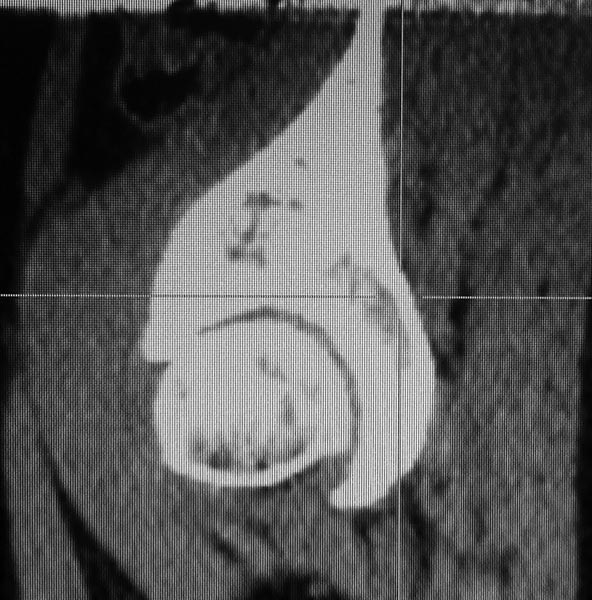

тут дисплазия и импинджемент больше cam type, на мой взгляд. Одного лечения импинджемента будет недостаточно, придется делать и периацетабулярную остеотомию - а это хирургия класса hi-end. В 48 лет не стал бы заморачиваться. Недавно запротезировал пациентку с очень похожей картинкой, долго ломал голову, но пациентка была из очереди на ВМТ и настаивала на протезе. Головка интраоперационно выглядела неважно.

Андрей, доброго Вам вечера. Боюсь что речь идет не о ФАИ, а о банальном диспластическом коксартрозе у женщины 48 лет. Думаю что ПАО делать уже поздно, поэтому если есть выраженный болевой с-м, ограничение движений, больная принимает НПВП, то надо думать об эндопротезировании тазобедренного сустава